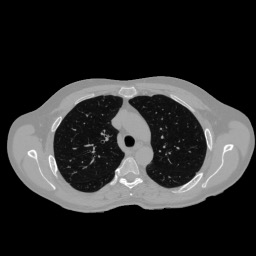

Anatomically consistent field-of-view (FOV) completion to recover truncated body sections has important applications in quantitative analyses of computed tomography (CT) with limited FOV. Existing solution based on conditional generative models relies on the fidelity of synthetic truncation patterns at training phase, which poses limitations for the generalizability of the method to potential unknown types of truncation. In this study, we evaluate a zero-shot method based on a pretrained unconditional generative diffusion prior, where truncation pattern with arbitrary forms can be specified at inference phase. In evaluation on simulated chest CT slices with synthetic FOV truncation, the method is capable of recovering anatomically consistent body sections and subcutaneous adipose tissue measurement error caused by FOV truncation. However, the correction accuracy is inferior to the conditionally trained counterpart.